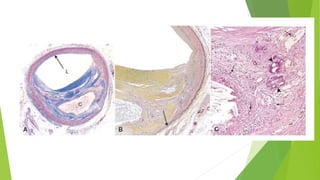

las placas tienden a producirse en los orificios de los

vasos existentes, los puntos de ramificacion, y a lo

largo de la pared posterior de la aorta abdominal,

donde existen patrones alterados de flujo.

 Aterosclerosis afecta fundamentalmente a las arterias elásticas (p. ej., aorta,

carótida y arterias ilíacas) y a las arterias musculares de tamaño mediano y

grande (p. ej., coronarias y poplíteas).

las placas tiendena producirse en los orificios de los vasos existentes, los puntos de ramificacion, y a lo largo de la pared posterior de la aorta abdominal, donde existen patrones alterados de flujo.

 Aterosclerosis afectafundamentalmente a las arterias elásticas (p. ej., aorta, carótida y arterias ilíacas) y a las arterias musculares de tamaño mediano y grande (p. ej., coronarias y poplíteas).  La enfermedad aterosclerótica sintomática afecta con mas frecuencia a las arterias que irrigan el corazón, el cerebro, los riñones y las extremidades inferiores.